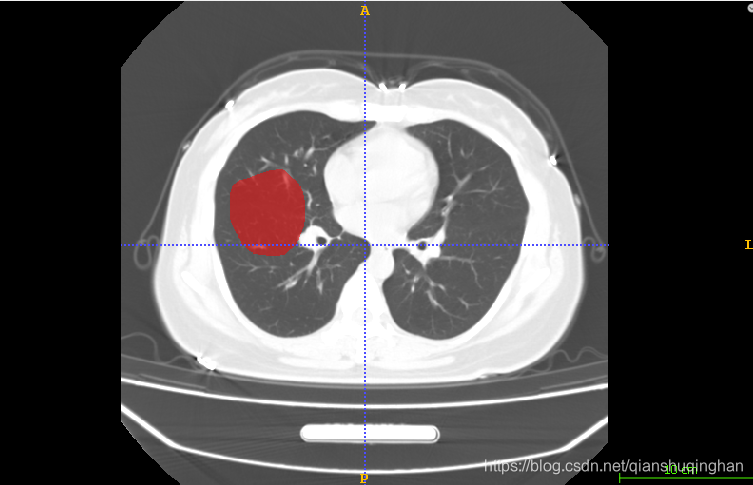

勾画对应病灶前,记得先选择病灶的类型label(软件左下角):Active Label

勾画病灶区域

选择勾画工具,分为画刷和画笔两种,左侧为画笔,按住左键勾画闭合轮廓后确认即可填实、得到目标区域;右边为画刷,需要手动完整涂抹目标区域:按住左键涂抹、按住右键擦除。

可选择不同的画笔模式,平滑折线或者间断折线

绘制闭合轮廓:

点击accept